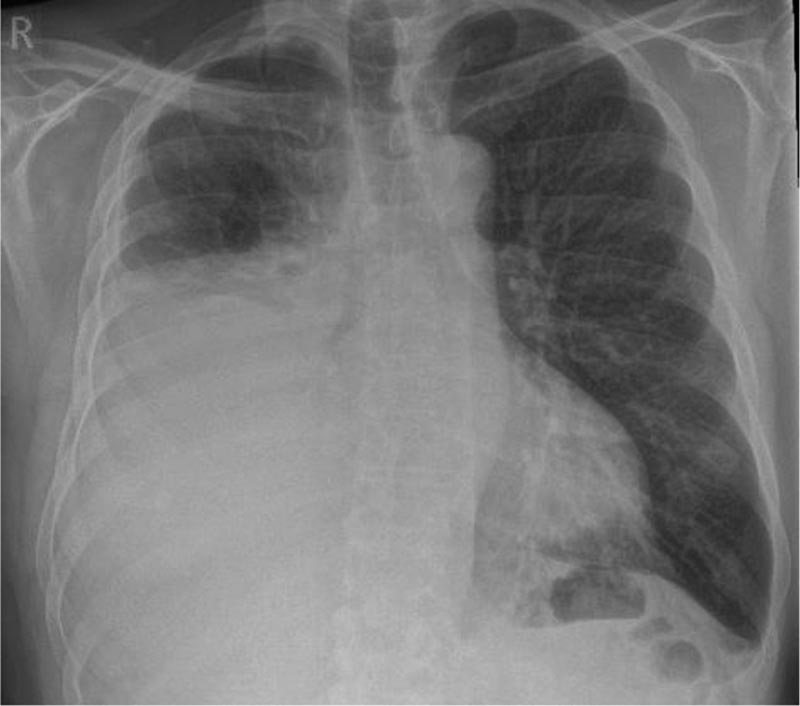

Presentazione di un caso Un uomo di 67 anni con una storia di fibrillazione atriale trattata con edoxaban che aveva iniziato a peggiorare 4 settimane prima della visita, con difficoltà respiratorie. È un fumatore e consuma 40 pacchetti all’anno. Ha avuto precedenti esposizioni all’amianto a causa del suo lavoro di costruttore. Il medico ha richiesto una radiografia del torace che mostrava un versamento pleurico unilaterale (destro) di dimensioni moderate. |

Figura 1: radiografia iniziale del torace